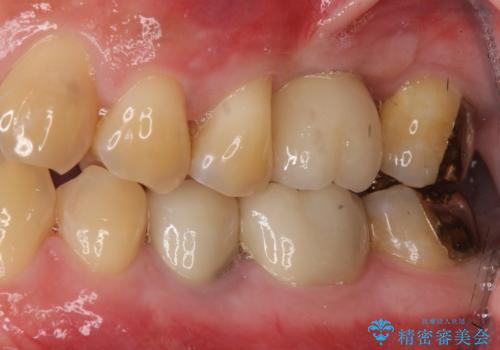

[歯の破折] インプラント埋入を行うための大規模骨造成